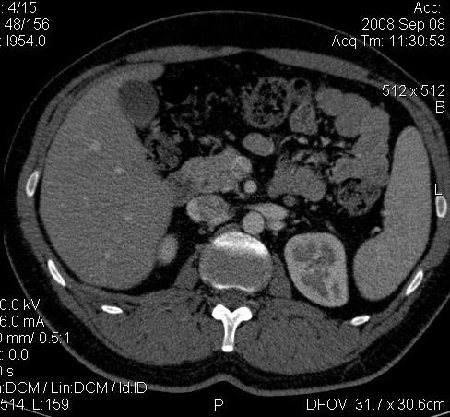

КТ Почек- подкова и уретеролитиаз

Данное наблюдение весьма демонстративно само по себе.

Ну ладно, раз никто больше не хочет, то отвечу свою версию - аномалия развития - подковообразная почка (horseshoe kidney).

Да красивая подковообразная почка - встречала раз 6-7.

Не вызывает сомнений. Картинка замечательная. Должно быть хорошо видно и на УЗИ.

Почечная колика; на последнем аксиальном скане чётко виден мелкий (2 мм) камень в устье правого мочеточника.

Для невладеющего КТ,очень четка видна аномалия на 3-4х снимках.А вот на 4-м скане в проксим.сегменте цистоида тоже есть гиперденсное точечное образование-не камень случайно?